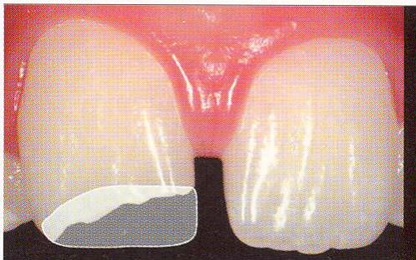

ところが、これは接着の技法の向上からでしょうか。殆ど削らずにすみます。そしてその日にできる可能性が大なのです。

その日に出来上がり硬い、色が綺麗